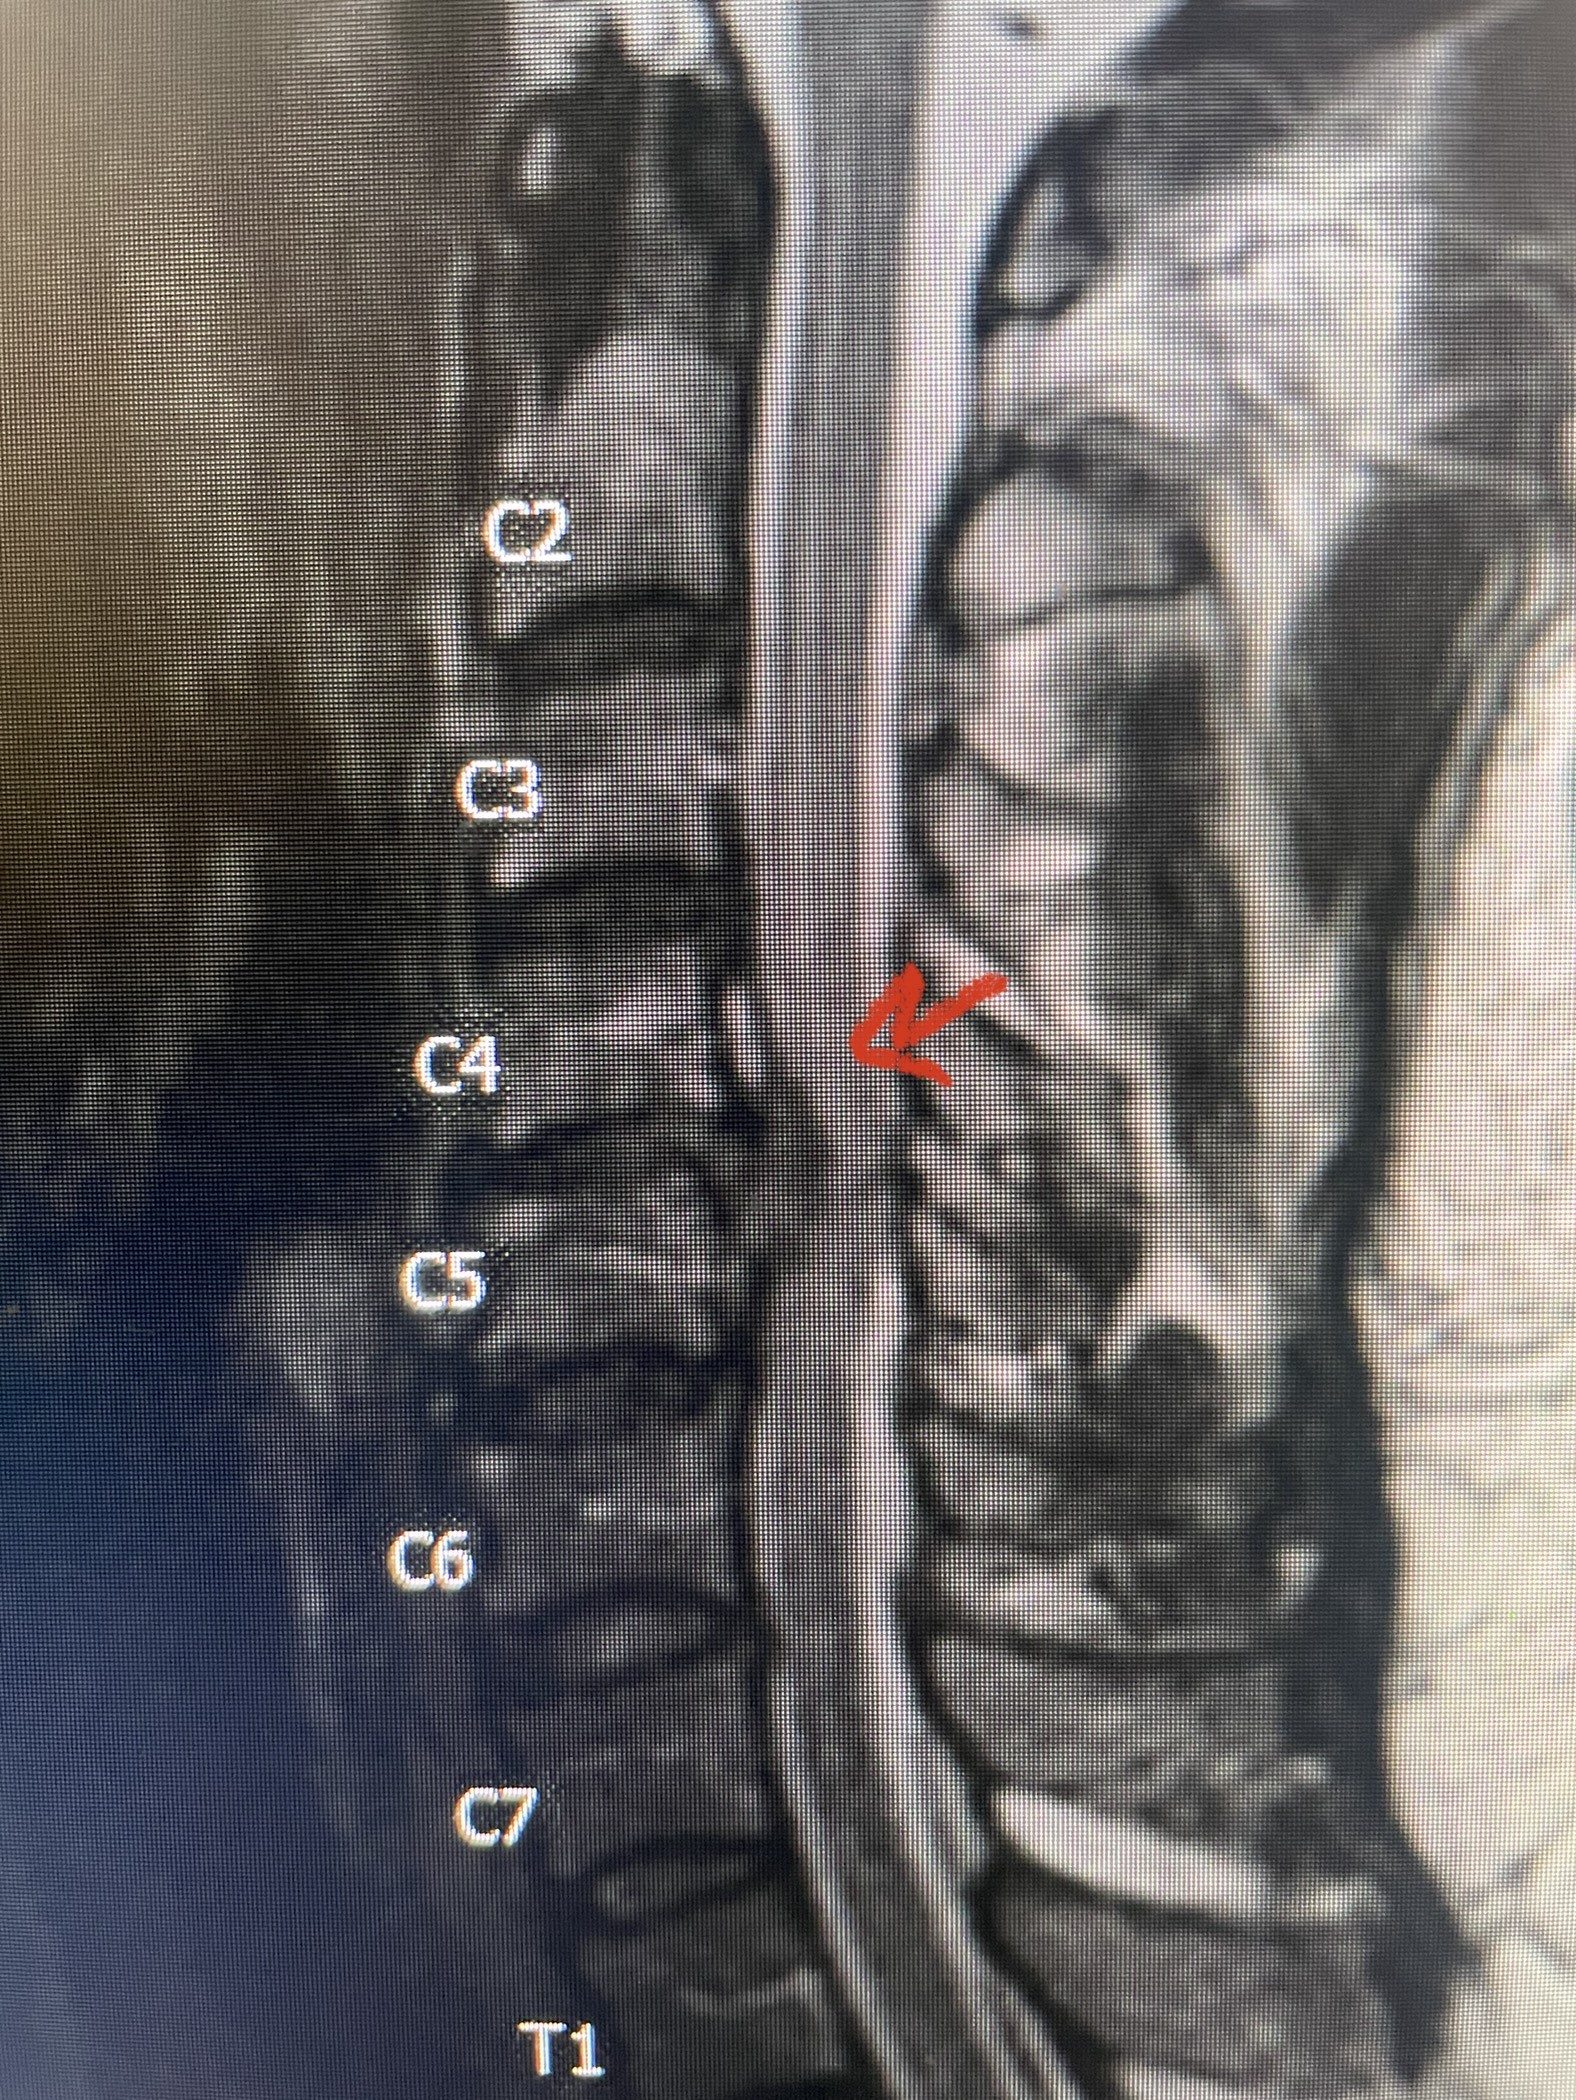

NSPC’s August 2023 Newsletter features four interesting and distinct case studies, including actual surgical footage from Dr. Zachariah George’s resection of thoracic intradural extramedullary lesion.